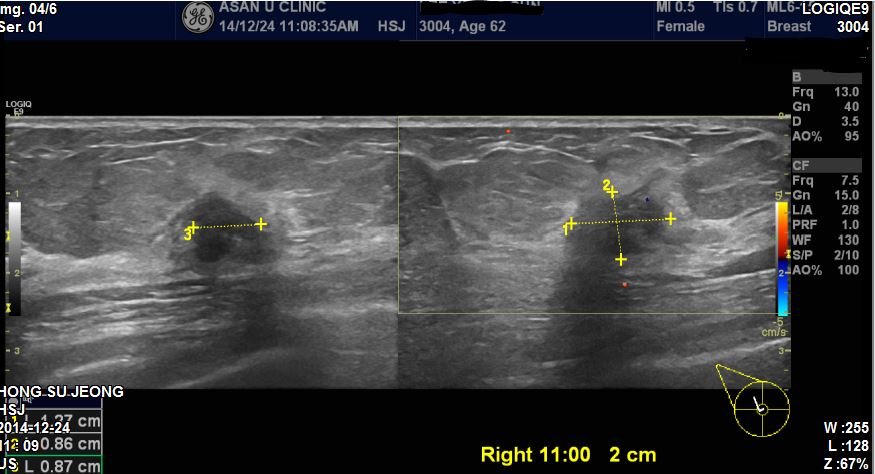

우측에 만져지는 멍우리로 내원하신 62세 환자분이십니다

초음파 시행 후 조직검사 시행하였고 결과 침윤성유방암으로 진단되었습니다